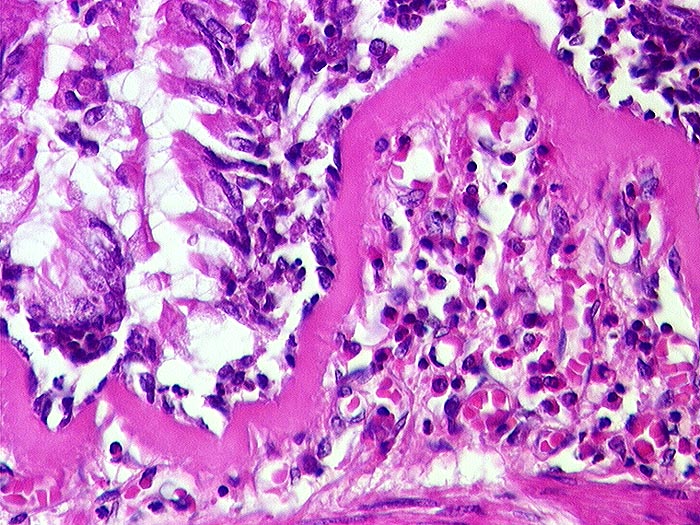

Asthma bronchiale

Bronchiolus mit starker Verdickung der Basalmembran und subepithelialem lymphoplasmazellulärem Entzündungsinfiltrat unter Beteiligung eosinophiler Granulozyten.

Tod im Asthmaanfall bei bekanntem Asthma bronchiale.

Histologie